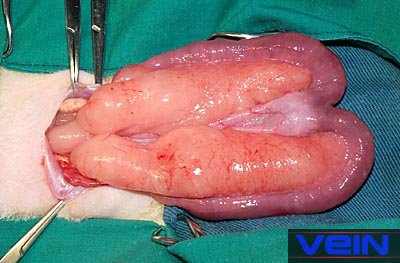

amelyeket a méh csatorna nem képes megfelelően elvezetni. Ez a méh

hatalmas megduzzadásához vezet, és kockázata a szakadás.

a petefészkekben tályog képződéséhez vezet. A méh kitágult, és általában tele gennyel. Akut fertőzéseket gyakran kíséri egy hüvelyi

Az anya nyúl diagnózisa: A duzzadt méhet gondosan meg kell vizsgálni, mivel a kitágult membrán törékeny. Méh tapintása segít meghatározni, az összhangot: sima vagy tésztás. Ha has megnagyobbodást diagnosztizálnak,

az alhas röntgene további információkat nyújthat. Ultrahangos képalkotás segít kizárni más méh betegségeket,